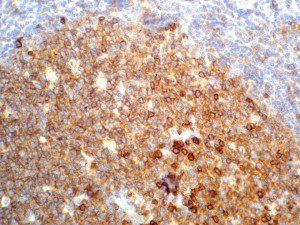

The first cytokines released are interleukin 1β (IL-1β) and tumor necrosis factor-α (TNF-α), which attract a variety of circulating white blood cells (WBCs) to the infection site, including neutrophils, monocytes, macrophages, and natural killer (NK) cells. This response, along with the antipathogenic chemicals released by these cells (i.e., complement), comprise the innate immune response. These cells directly attack the invading pathogen and also release additional cytokines, chief among them interleukin-1 and 6 (IL-6). IL-6 is essential for invoking the adaptive immune response, which calls T-cells, B-cells, and T helper (Th) cells to the infection site. IL-6 also stimulates further recruitment, proliferation and activation of macrophages.

It is the ICU physician who is most likely to witness one of the deadliest manifestations of the abnormal immunological response, the cytokine storm syndrome (CSS). This response is also referred to by some as the cytokine release syndrome (CRS). CSS is characterized by continuous activation and expansion of macrophage and lymphocyte populations, which secrete large amounts of cytokines, causing the cytokine storm. This massive cytokine release is akin to hemophagocytic lymphohistiocytosis (HLH) disease, a syndrome characterized by initial unchecked and persistent activation of cytotoxic T lymphocytes and NK cells.